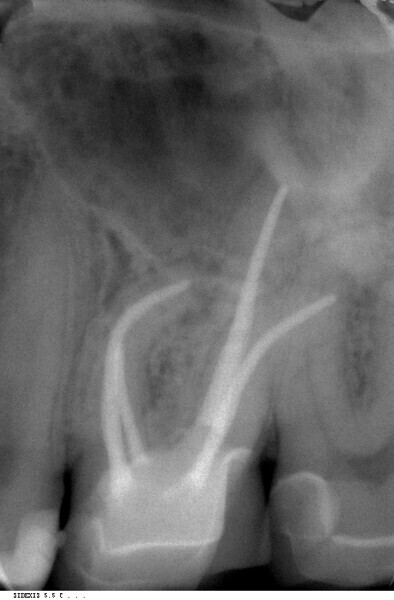

Endodontic follow-up in strongly curved root canals